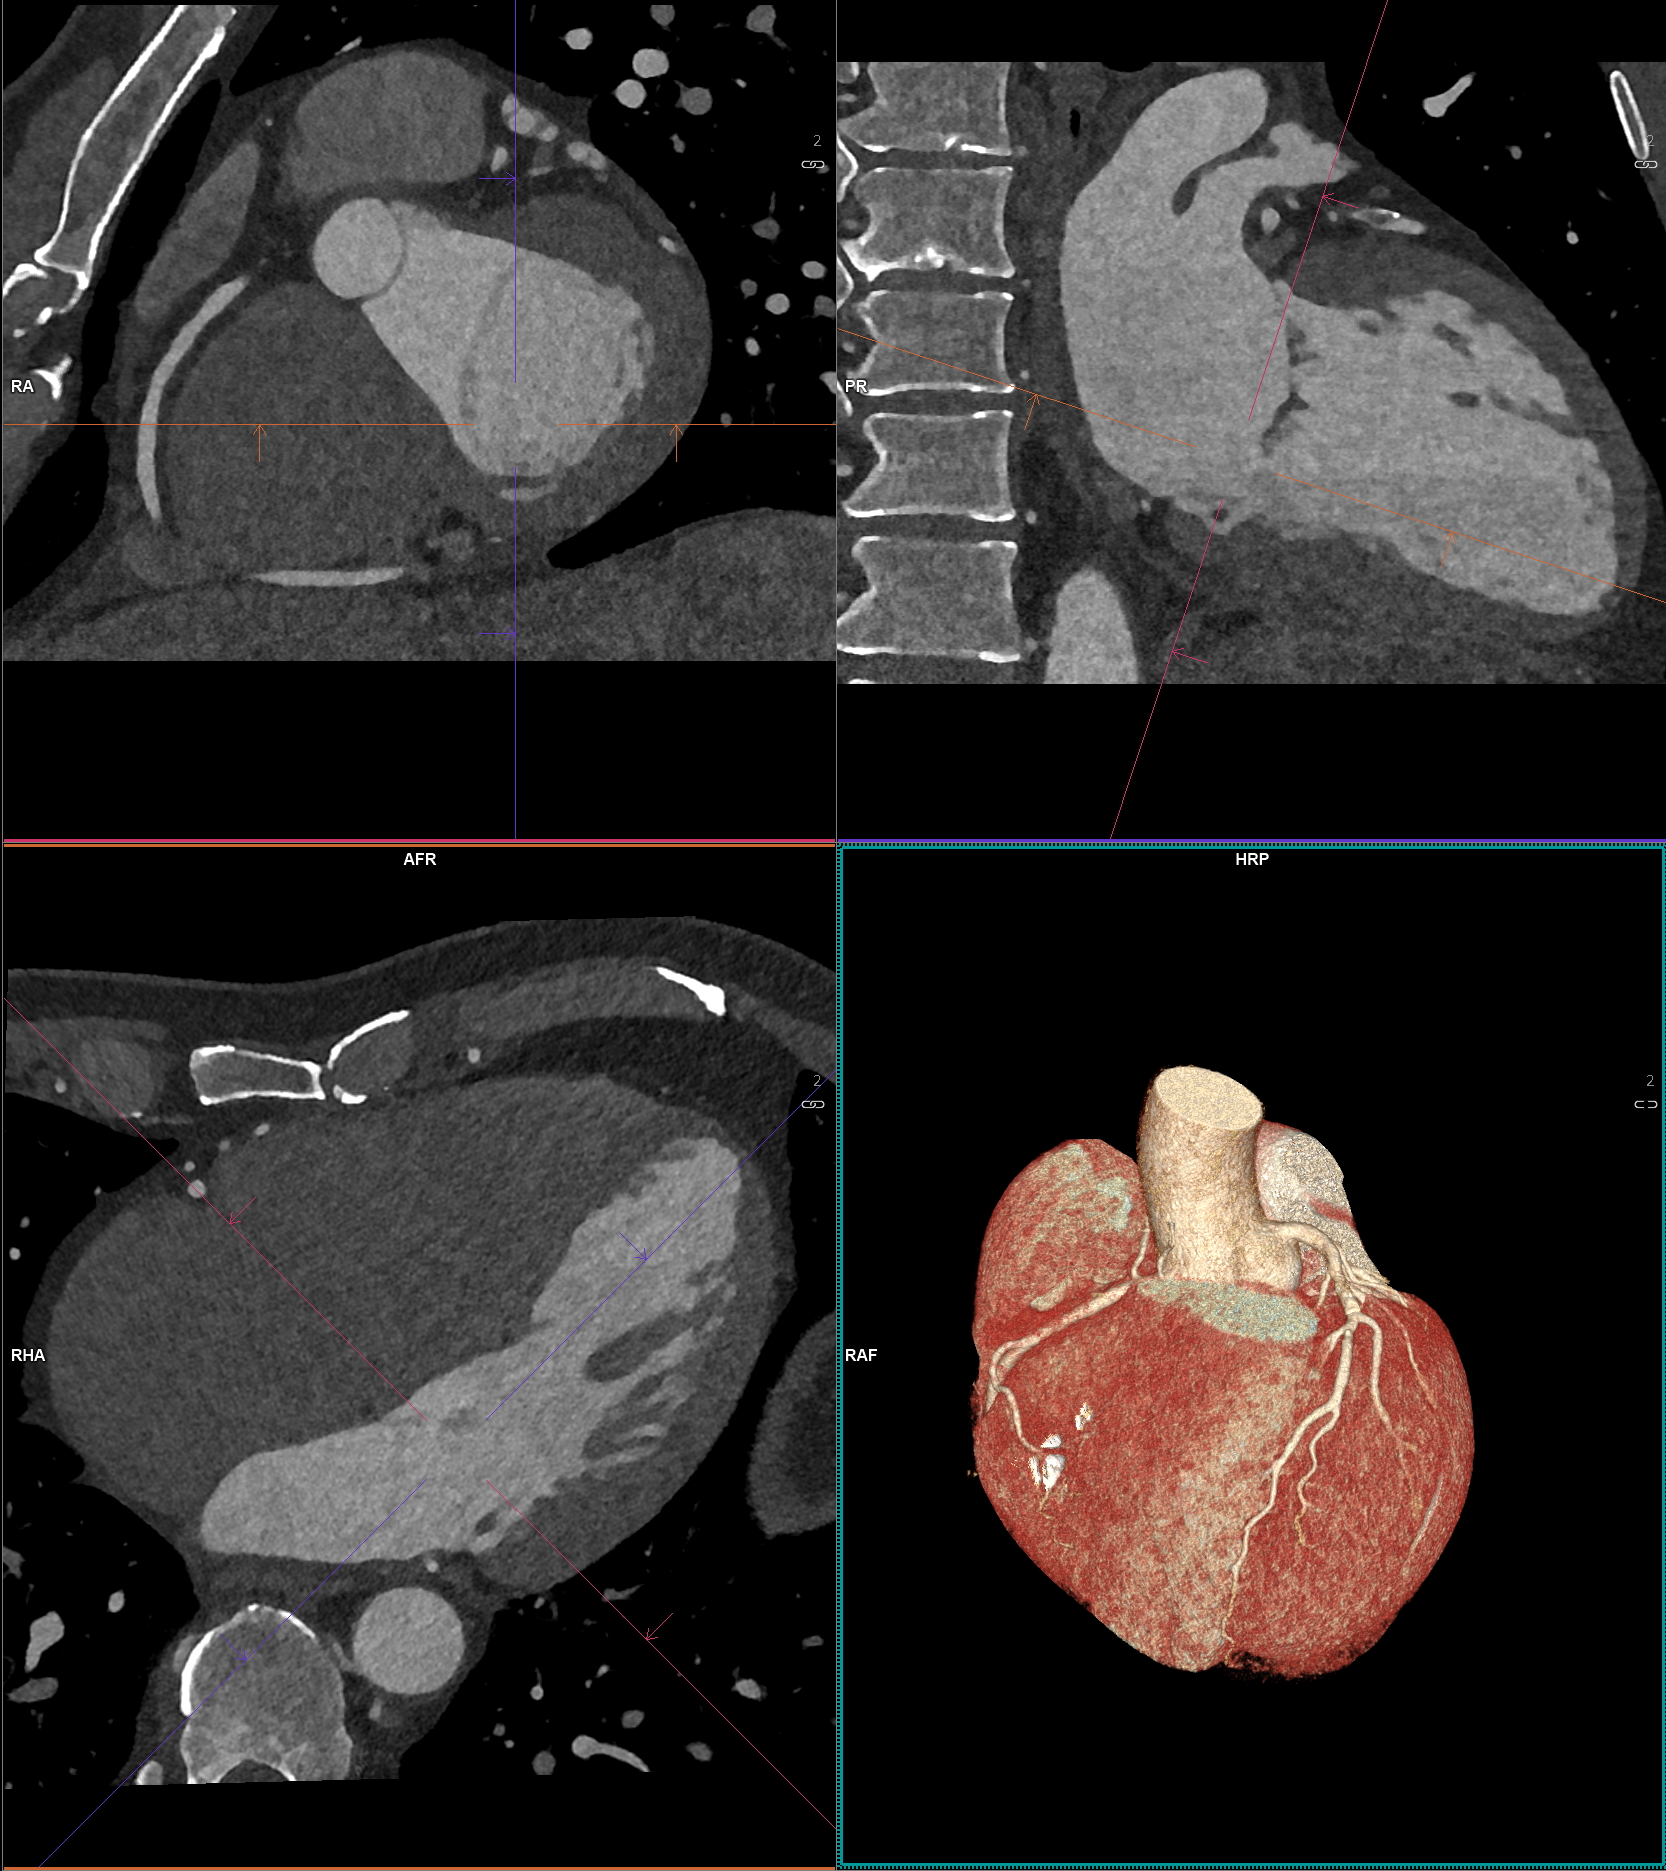

Placken kan bestå av mjukare plack eller förkalkade plack. Mjukare plack innehåller fett och kolesterol, men syns inte på en Calcium score undersökning. Förkalkade plack innehåller kalcium, vilket gör dem hårdare och synliga vid både DT-Hjärta och Calcium score.

När placken växer kan de tränga in i kärlets lumen (den öppna kanalen där blodet flödar) och orsaka förträngningar. Detta kan försämra blodflödet till hjärtat, vilket i värsta fall leder till kärlkramp eller hjärtinfarkt. Det mest riskfyllda är dock att ett plack kan brista. Då kan en blodpropp snabbt bildas och helt blockera blodflödet i kranskärlet – det är ofta detta som orsakar en akut hjärtinfarkt.

Hjärtscanning kan påvisa huruvida du har ateroskleros (åderförfettning eller åderförkalkning). Det finns två olika metoder. Den enklaste varianten mäter förekomst av förkalkningar i kranskärlen, så kallat ”coronary artery calcium score”. Det finns ett starkt samband mellan calcium score, mängden ateroskleros och framtida risk för hjärtkärlsjukdom. 5-10% med ateroskleros har plack utan förkalkning och dessa syns inte vid användande av calcium score. Dessa plack är i regel farligare än de med förkalkning i sig. För att även kunna se dessa förändringar behöver man göra en datortomografi av kranskärl där man tillför kontrastmedel vilket är den andra metoden - Datortomografi av hjärtat.